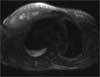

Results of a basic metabolic panel are normal except for a blood glucose level of 228 mg/dL. White blood cell count is elevated at 12,900/μL, with 80% polymorphonuclear leukocytes and 2% band forms. Creatine kinase level is 226 U/L. Ultrasonography of the breast shows diffuse edema of the upper outer quadrant of the right breast without evidence of breast abscess. Chest CT scan with contrast and T2-weighted MRI scan of the right pectoralis musculature are shown.

The CT scan of the chest shows increased subcutaneous stranding of the right breast and enlargement of the pectoralis major, with shotty axillary lymphadenopathy (Figure 1). The MRI scan demonstrates myositis of the right pectoralis with an 11 x 2-cm area of lack of enhancement, which is consistent with either necrosis or abscess within the muscle (Figure 2).

Diabetic muscle infarction (choice A) is a noninfectious complication of chronic uncontrolled diabetes. As with the other causes of myositis, diabetic muscle infarction produces isolated muscle inflammation that results in pain, swelling, and erythema. MRI typically demonstrates an area of lack of enhancement similar to the one seen on this patient’s MRI scan. However, fever, leukocytosis, and abscess are not characteristic of diabetic muscle infarction.